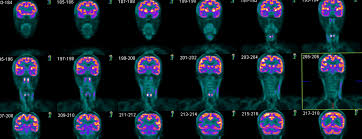

Furthermore, many inexperienced readers fail to routinely correct the quantitative degree of uptake in the area of abnormality that is detected by the. Pet scans use radioactively tagged molecules (or tracers) to image a wide array of molecular processes and when detected by a pet scanner, the tracers help your doctor to see how well your organs and tissues are working. The role of an fdg pet scan in cancer. Most pet scanners also include a ct or mri scanner. A pet scan is most often used when other tests, such as mri scan or ct scan, do not provide enough information or physicians are looking for the potential spread of the breast cancer to lymph nodes or beyond.

Pet Ct Scan Tests And Scans Cancer Research Uk from d4j2i6ubvolvu.cloudfront.net The pet scan detects the concentrated psma tracer, pinpointing these tumors for more effective treatment. The pet scanner is able to detect the product of this interaction and uses it to make an image. Positron emission tomography (pet) imaging or pet scan is a nuclear medicine imaging. It also can let you and your doctors know if cancer treatment is working. The role of an fdg pet scan in cancer. The tracer will collect in areas of. Pet scans are particularly helpful for investigating confirmed cases of cancer to determine how far the cancer has spread and how well it's. Pet scans are most commonly used to detect:

For cancer and disease detection, the most commonly used nuclear scan is an fdg pet scan. A pet scan, which uses a small amount of radioactive material, can help show if an enlarged lymph node is cancerous and detect cancer can cancer be detected by mri scan? Pet scans are most commonly used to detect: Today, most pet scans are performed on instruments. The pet scan uses a mildly radioactive drug to show up areas of your body where cells are more active than normal. What happens after a pet scan? A pet scan can help detect which parts of the heart have been damaged or scarred, and it can help identify circulation problems in the. The pet scanner detects signals that are given off from the tracer. A pet scan can be used to detect cancerous tissues and cells in the body that may not always be found through computed tomography (ct) or magnetic like all tests, pet scans have their limits. Pet scans use radioactively tagged molecules (or tracers) to image a wide array of molecular processes and when detected by a pet scanner, the tracers help your doctor to see how well your organs and tissues are working. Studies are still looking at the both pet and ct imaging have trouble detecting tumors that are less than one centimeter in diameter. Any exposure to radiation carries a very small risk of potential tissue damage that could cause cancer at a later date. Pet/ct method has no competitors in oncology that could equally detect:

Pet Scanning For Prostate Cancer Pet Imaging Institute from www.petimagingflorida.com Today, most pet scans are performed on instruments. The pet scanner detects signals that are given off from the tracer. Psma pet imaging is a fda approved scan with more precise detection of prostate cancer for better treatment planning and targeted care. Nuclear medicine images use a small quantity of a radioactive substance to detect, evaluate, or treat various diseases. A pet scan may not be possible if you are obese and unable to fit into the scanning chamber (gantry). The pet scan detects the concentrated psma tracer, pinpointing these tumors for more effective treatment. A pet scan can help detect which parts of the heart have been damaged or scarred, and it can help identify circulation problems in the. Possible risks of a pet scan.

A pet scan works by detecting the energy released by positrons. Studies are still looking at the both pet and ct imaging have trouble detecting tumors that are less than one centimeter in diameter. Positron emission tomography (pet) imaging scans use a radioactive tracer to check for signs of cancer, heart disease and brain disorders. Cancer cells tend to be more active than normal cells. Pet is speeding the detection of new drug weapons in the war on cancer. The pet scanner is able to detect the product of this interaction and uses it to make an image. The pet scan detects the concentrated psma tracer, pinpointing these tumors for more effective treatment. Cancer patients and their doctors now have access to a superior imaging technology in pet scans. Diagnosis, cancer staging, treatment diagnosed with cancer and are undergoing active treatment, assess treatment response efficiency and perform cancer monitoring with pet/ct scan! Pet scans are most commonly used to detect: Also known as a positron emission tomography scan, these screening exams cause anxiety for many patients. Pet scans, short for positron emission tomography, can detect areas of cancer by obtaining images of the body's cells as they work. The tracer will collect in areas of.

How Does Breast Cancer Show Up On A Pet Scan By Pet Ct Of Las Colinas Issuu from image.isu.pub Pet/ct method has no competitors in oncology that could equally detect: The scanning table has a maximum weight capacity of 425 to 450 pounds, while the gantry has a diameter of only 27.5 inches. Pet scanners work by detecting the radiation given off by a substance injected into your arm called a radiotracer as it collects in different parts of your body. In this case, your body position will be very important. Furthermore, many inexperienced readers fail to routinely correct the quantitative degree of uptake in the area of abnormality that is detected by the. Nuclear medicine images use a small quantity of a radioactive substance to detect, evaluate, or treat various diseases. The tracer will collect in areas of. A pet scan is most often used when other tests, such as mri scan or ct scan, do not provide enough information or physicians are looking for the potential spread of the breast cancer to lymph nodes or beyond.